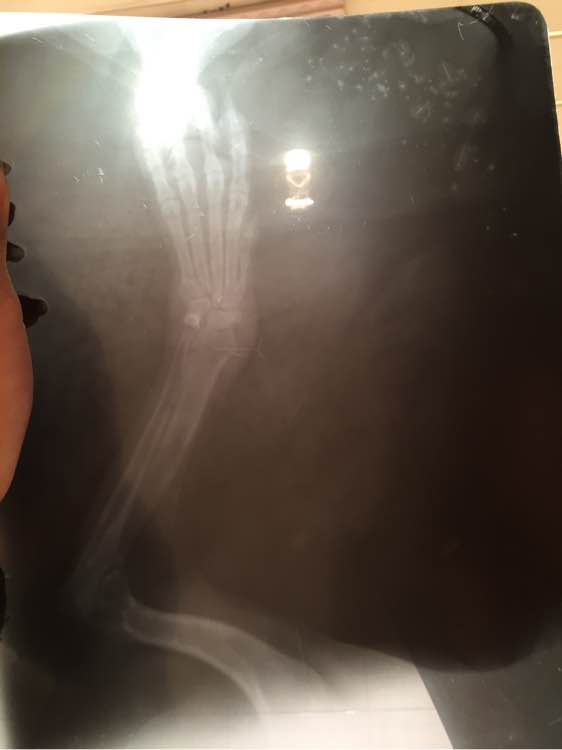

网友也不敢轻举妄动,于是下午就带了狗狗去医院拍了片子。检查出来的结果让所有人吃惊,原来狗狗的肚子里还有孩子,但是是死胎!于是网友按照医生的嘱咐,准备安排明天动手术。

结果第二天的手术很顺利,照片中的狗狗在手术后麻醉还没有醒过来,看起来很萌。医生说狗狗有点胖,等身体康复了不要吃太多,减肥节食才行。